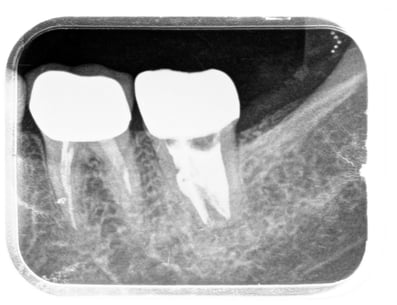

ガッタパーチャを完全に除去し、別の薬に置き換えました。別の薬が根の先まで到達しているのがわかると思います。